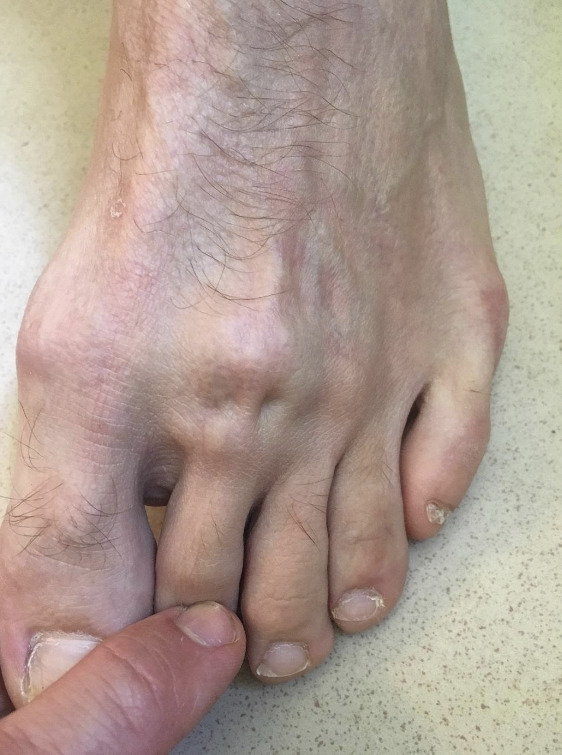

L’examen met en évidence une tuméfaction solide et une douleur à la palpation au niveau de la tête du 2e méta­tarsien. La flexion des orteils dévoile une dépression au niveau de l’articulation métatarsophalangienne, laissant apparaître très nettement le tendon extenseur qui semble en suspension (fig. 1).